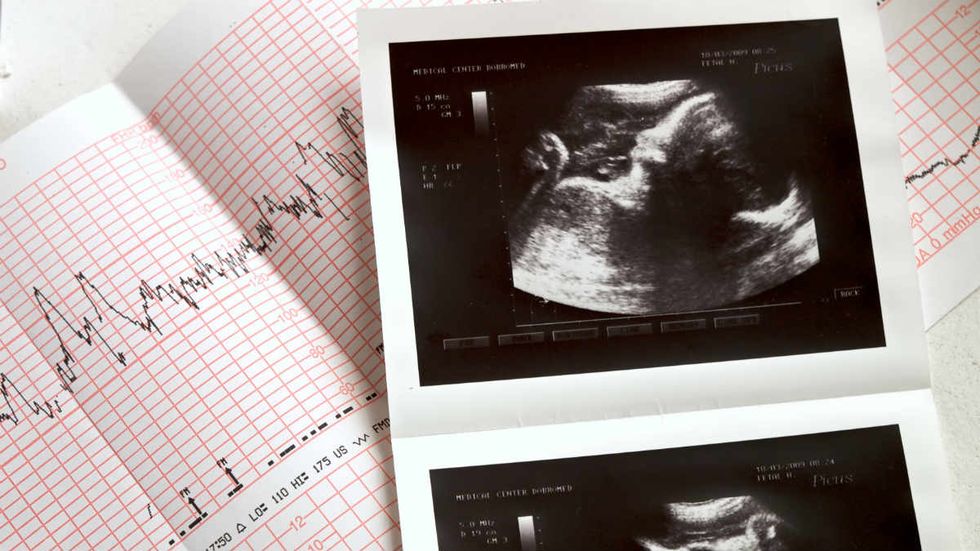

Ohio's law bans abortion at six weeks, the point where an unborn child's heartbeat can be detected. A federal judge appointed by George W. Bush ruled Wednesday that that restriction ran up against Supreme Court precedent set in case of Planned Parenthood vs. Casey, under which states cannot impose an "undue burden" on abortion access.